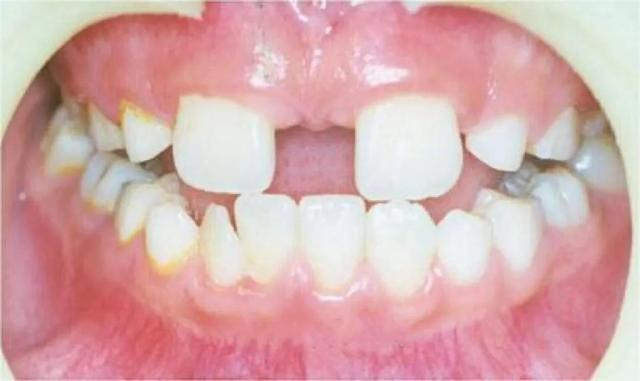

医生,我家小孩8岁多了,这两颗上门牙换了很久了,缝隙怎么还这么大啊?

我们先给小朋友拍个全景片看一下是不是有多生牙吧。

小朋友家长,这是刚拍好的片子,请看这个地方,是因为长了多生牙才影响了正常恒牙的位置,导致两颗牙齿之间的间隙过大。

3 牙间隙大